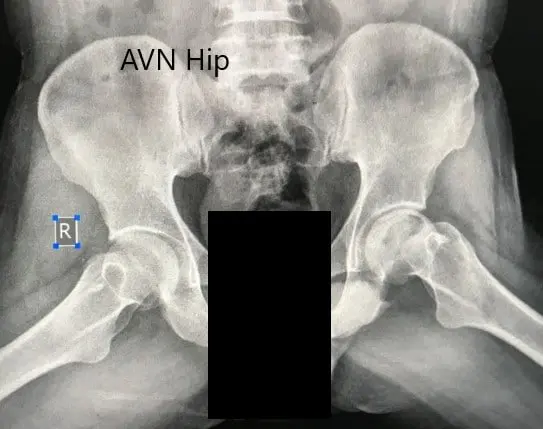

A routine blood examination was done to estimate the levels of serum vitamin D and electrolytes. Imaging studies in the form of X-Ray revealed increased sclerosis of the left hip. A small radio-opacity was present just below the superior surface of the head of the femur. There were moderate acetabulum changes.

Preoperative X-ray of the pelvis with both hips in anteroposterior view showing AVN of the Left Hip.